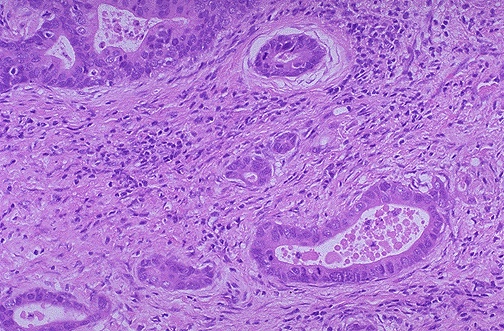

At higher magnification, the neoplastic glands of gastric adenocarcinoma demonstrate mitoses, increased nuclear/cytoplasmic ratios, and hyperchromatism. There is a desmoplastic stromal reaction to the infiltrating glands.